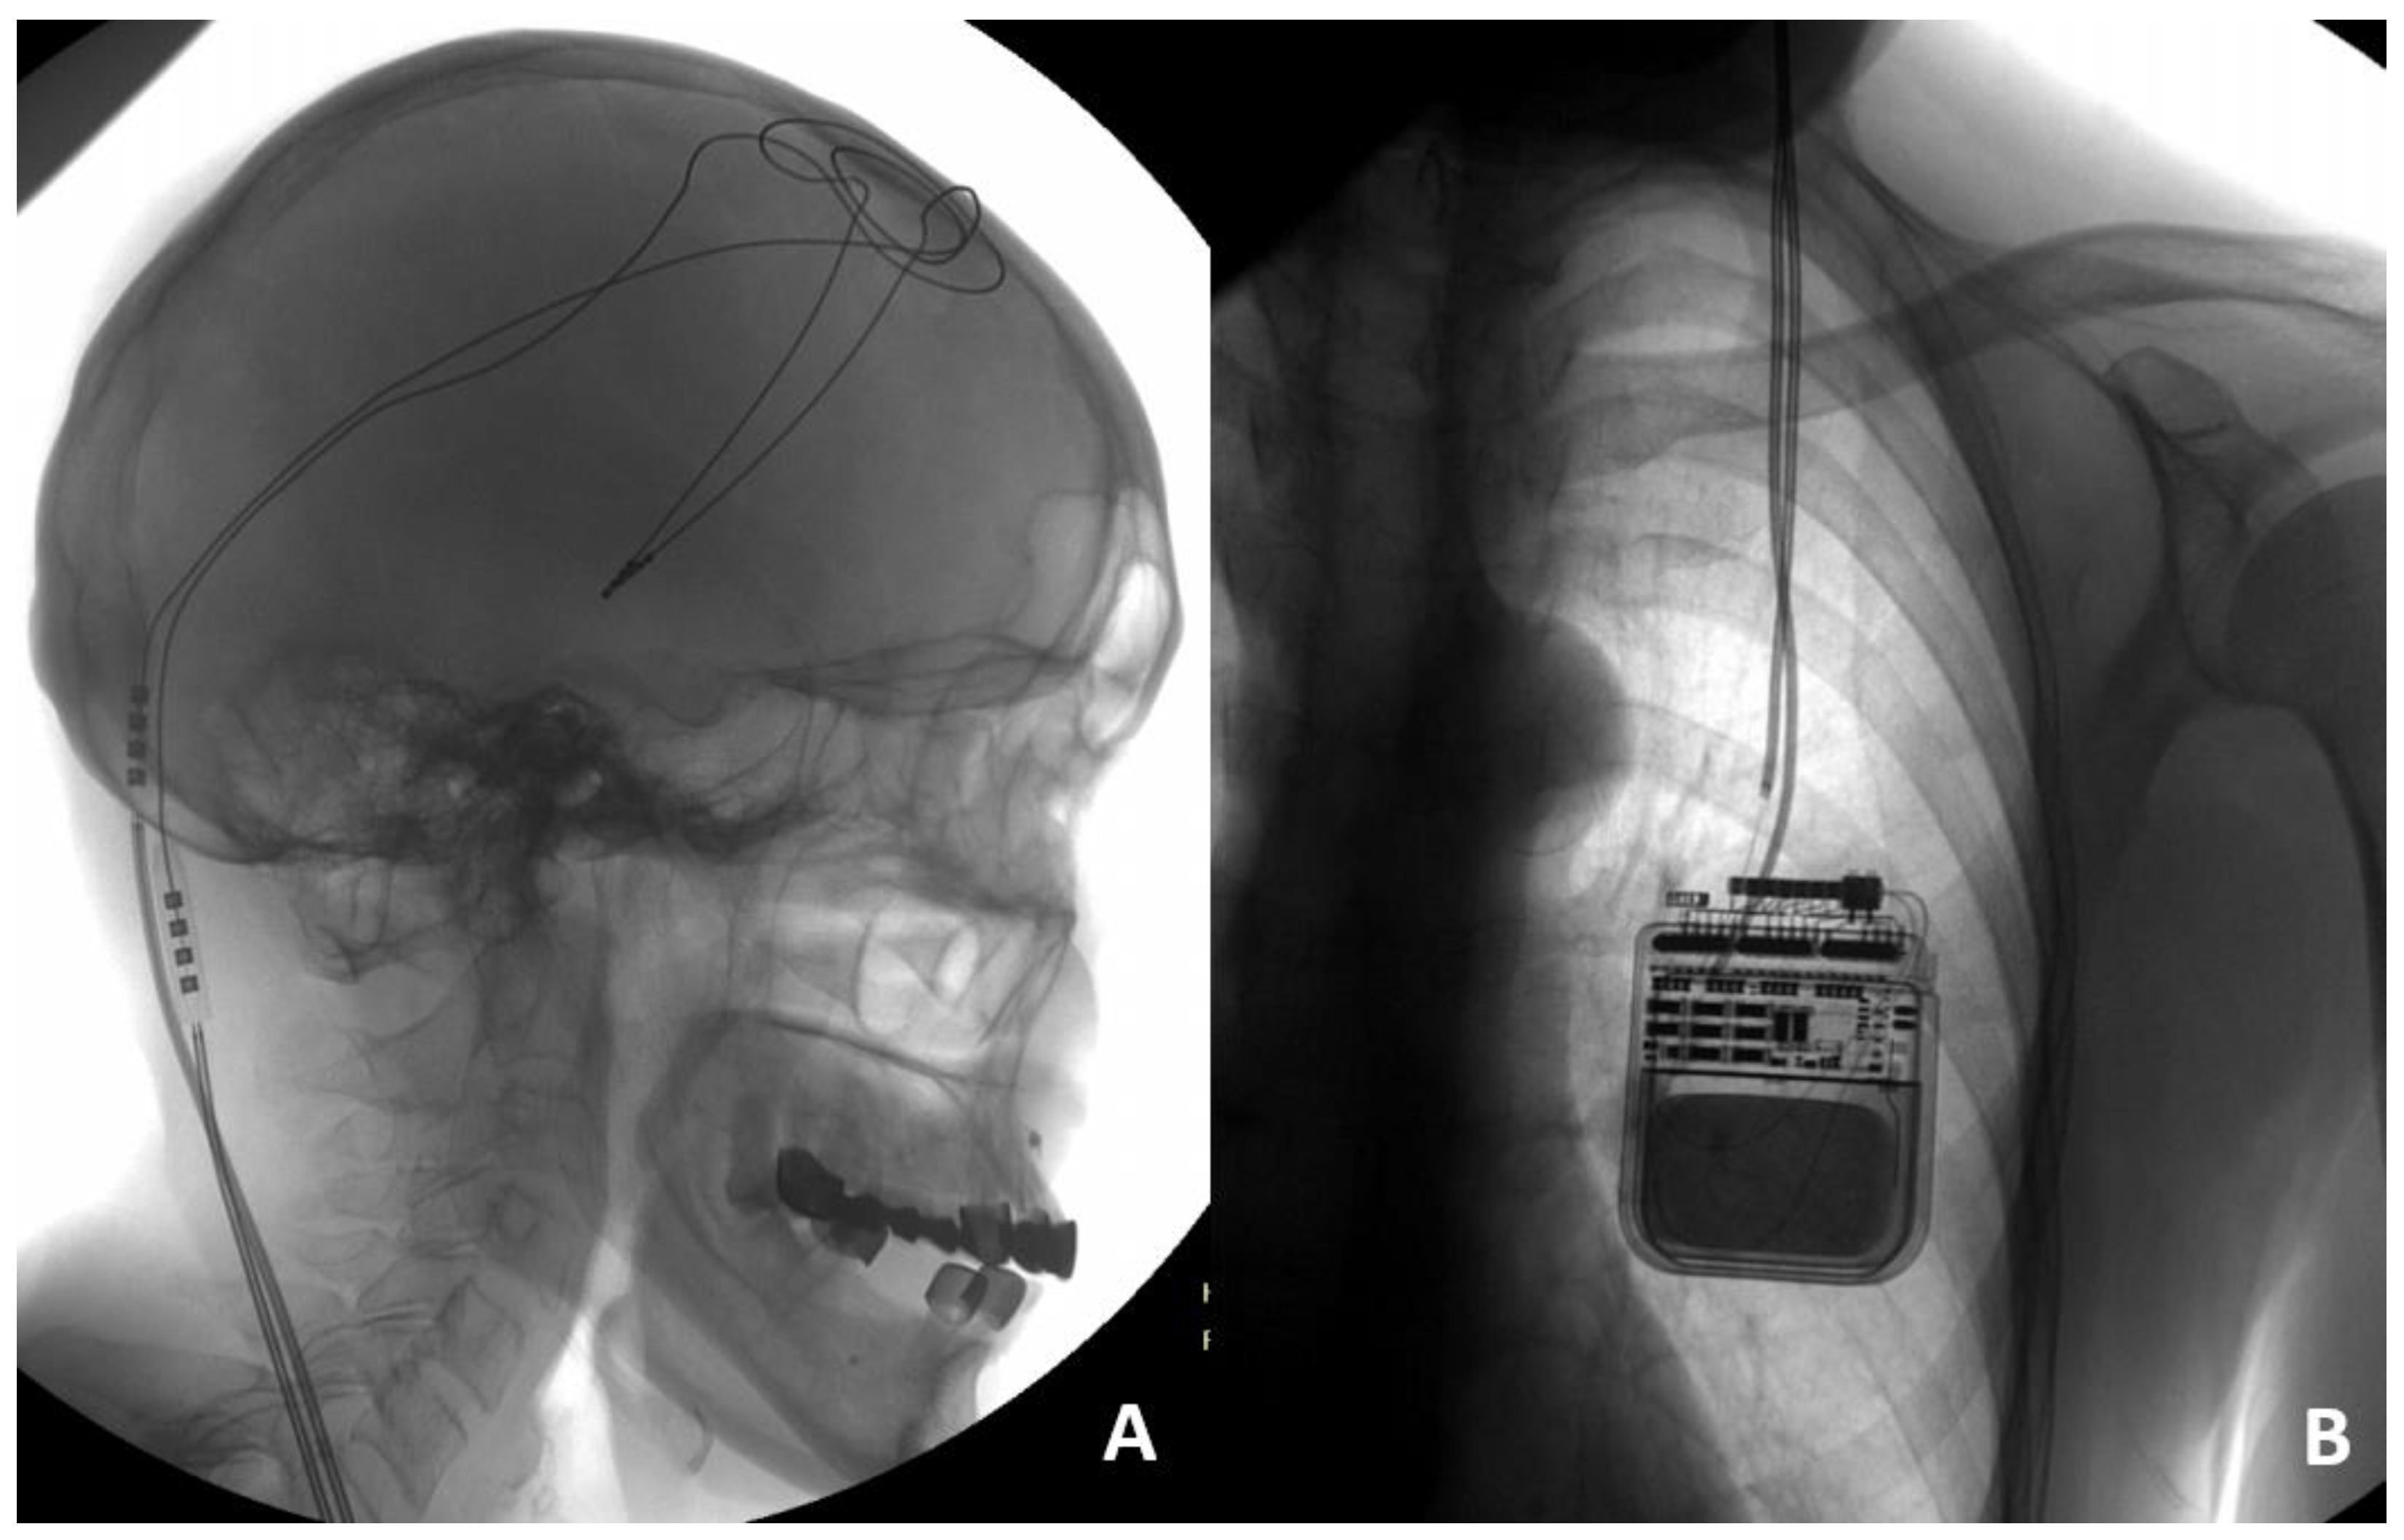

Illustrative case 2. Patient 12, a 63-year-old female diagnosed with stage 3 Parkinson’s disease according to the Hoehn and Yahr scale, has been managing her condition with bilateral STN DBS using a left dual-channel IPG (Activa PC) for two years. The initial programming of the DBS system yielded significant symptomatic improvement. Recently, the patient experienced a gradual worsening of her condition, notably two weeks following a fall. This decline in her condition necessitated a thorough evaluation to examine the functionality of the DBS system. Electrode impedance measurements for electrodes 8 through 10 were found to exceed 2000 Ω, suggesting a potential malfunction of the lead system. To ascertain the cause of the suspected malfunction, the patient underwent diagnostic imaging, including cranial and chest X-rays. The cranial and chest X-rays revealed no abnormalities in the hardware configuration (Figure 2A,B), suggesting that all DBS system components remained intact. However, due to acute worsening of the patient’s condition and lack of stimulation effect, a decision was made to revise the extensions, and an intraoperative incomplete left extension fracture in the neck region was found. After the diagnostic findings, surgical intervention was undertaken to replace the malfunctioning left extension wires. This corrective measure successfully restored the efficacy of the DBS therapy, evidenced by the patient regaining control over her tremors.

Illustrative case 4. Patient 14, a 57-year-old male diagnosed with Parkinson’s disease at stage 3 according to the Hoehn and Yahr scale, had been managing his condition effectively for eight years. The patient had undergone bilateral STN DBS with IPG (Scene Ray Aaxon) for one year, witnessing sustained improvement in motor symptoms. Stability in motor function was abruptly compromised following a trauma incurred during physical exercise, specifically pull-ups. This incident prompted an immediate evaluation of the DBS system to ascertain the impact of the trauma on its functionality. Initial impedance and current measurements identified an open circuit condition in the electrodes targeting the left STN, characterized by impedance levels exceeding 2000 Ω and current measurements below 7 μA. Conversely, electrodes positioned elsewhere displayed normal operational metrics. Radiographic imaging of the chest and skull, aimed at identifying potential hardware deformities, yielded negative results (illustrated in Figure 4A,B), suggesting no visible structural damage to the system components. Given the diagnostic findings and the acute onset of symptoms post-trauma, an emergent surgical revision was deemed necessary. During the procedure, a fracture in the left DBS extension lead was identified at the junction connecting the extension wire to the pulse generator (Figure 4C). This mechanical failure was pinpointed as the critical factor undermining the system’s efficacy. The replacement of the left extension wire was performed, resulting in a significant improvement in the patient’s motor symptoms during subsequent follow-ups.

Figure 2. Skull X-ray illustrating intact DBS leads (A). Chest X-ray showing the lead fracture with connection located in subclavicular region (B).

Figure 4. Skull (A) X-ray showing any deformities of the leads. Chest (B) X-ray showing the reversed position of the extensions at the junction connecting to the IPG. Intraoperative view of the lead fracture at the point of connection between extension and IPG (C).